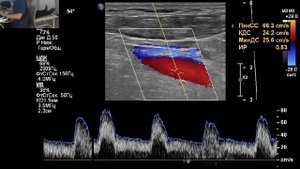

УЗИ сосудов шеи. В направлении - стеноз БЦ ствола. Я не обнаружил. Но есть много чего интересного...